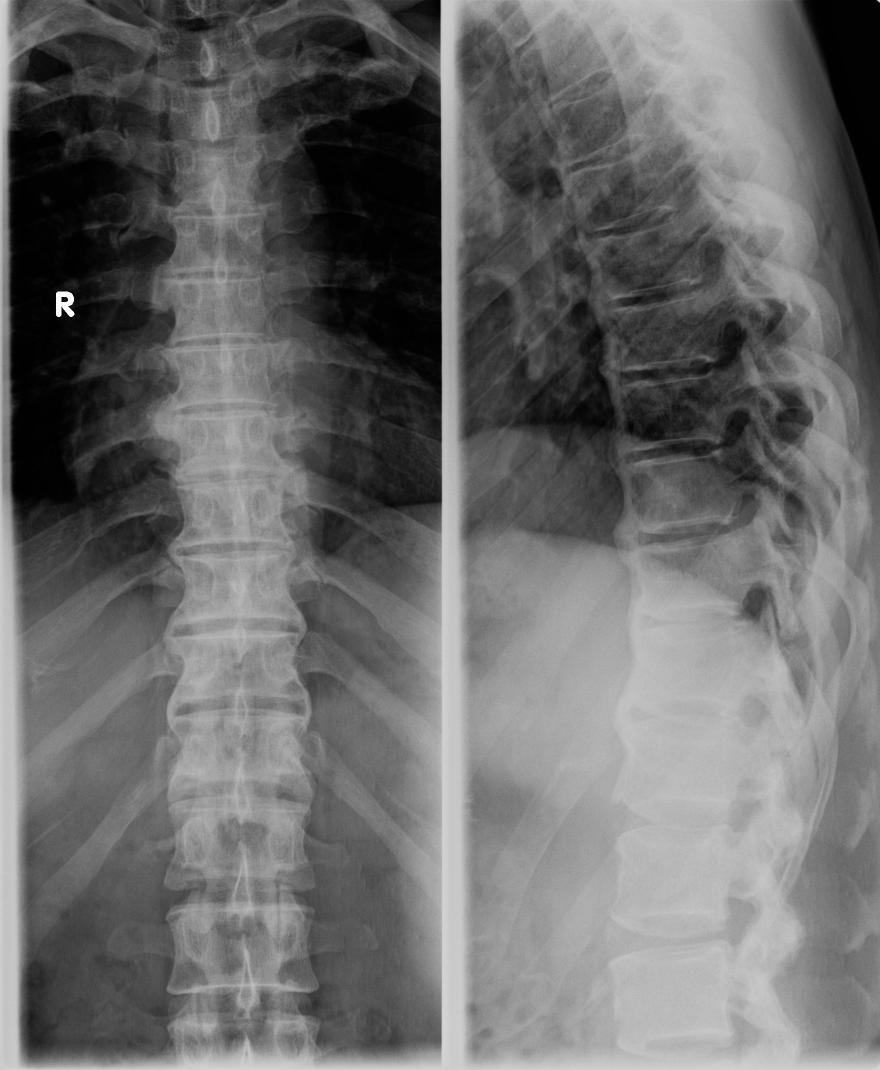

以下是引用zhangzhongshou在2007-12-9 12:45:00的发言:[br]典型弥漫性特发性骨质增生症,诊断依据年龄及影像表现,影像表现以胸椎前纵韧带广泛骨化为特征,椎体两侧缘亦见不规则骨化影,右侧较左侧著,可能与主动脉波动抑制了骨形成有关,显示腰椎大致正常,椎小关节未见明显异常。[br][br][本贴已被 zhangzhongshou 于 2007-12-9 13:41:29 修改过]